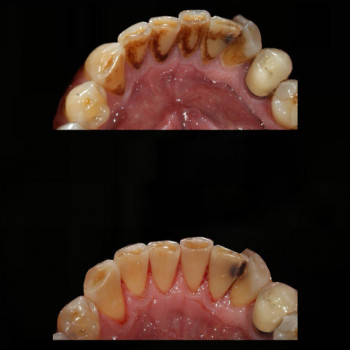

Лікування пародонтиту від 1 до 4 ступеня тяжкості у Хмельницькому Пародонтит – це запальне захворювання ясен і тканин, що утримують зуби. Без лікування воно прогресує від початкового нальоту й кровоточивості до серйозної втрати кісткової тканини та рухливості зубів. У нашій клініці ми проводимо комплексне лікування пародонтиту будь-якої стадії – від 1 до 4 ступеня тяжкості. ✔️ 1 ступінь – професійна гігієна, усунення нальоту, навчання догляду ✔️ 2 ступінь – кюретаж ясенних кишень, лікування запалення ✔️ 3 ступінь – комплексна терапія, шинирование, відновлення тканин ✔️ 4 ступінь – хірургічні методи, імплантація та протезування при втраті зубів Ми використовуємо сучасні методи: ультразвукову чистку, Air Flow, закритий кюретаж. Регулярне звернення до пародонтолога дозволяє зупинити прогресування хвороби, зберегти власні зуби та повернути здоров’я ясен. 👉 Запишіться на консультацію та лікування пародонтиту у Хмельницькому – відновіть здоров’я ротової порожнини на будь-якій стадії захворювання!

Відповідь: Виділяють 4 ступені: від легкої форми з нальотом і кровоточивістю до важкої – із втратою кісткової тканини та рухливими зубами.

Відповідь: Лікування включає професійну гігієну, кюретаж, комплексну терапію, шинування, а на пізніх стадіях – хірургію та протезування.